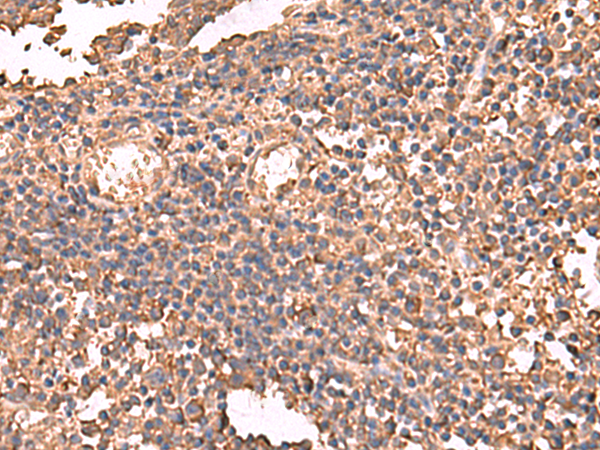

分类: 科研抗体货号: P10095别名: TEF5; TEAD5; TEF-5; DTEF-1; ETFR-1; TEAD-3应用: IHC反应种属: Human, Mouse